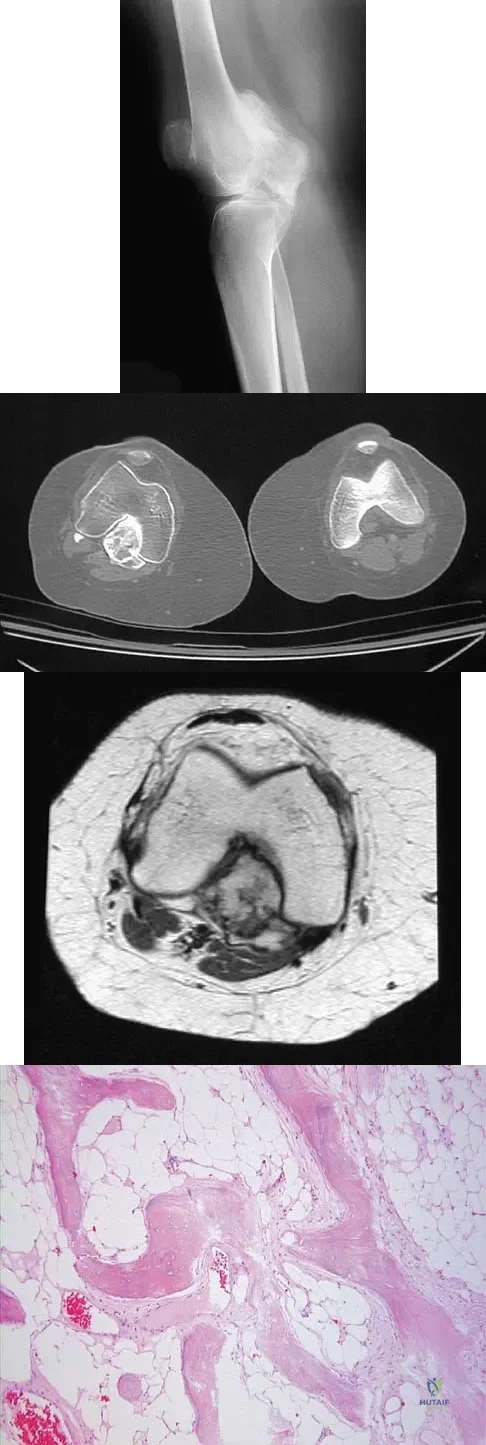

Question 16

A 25-year-old woman has had pain and stiffness in her knee following a motor vehicle accident 9 months ago. The radiograph, CT scan, MRI scan, and biopsy specimen are shown in Figures 53a through 53d. What is the most likely diagnosis?

Figures 56a through 56c show the radiograph, CT scan, and biopsy specimen of a 44-year-old man who underwent chemotherapy and radiation therapy for lymphoma of the distal femur 20 years ago. His current problem is most likely related to

Explanation